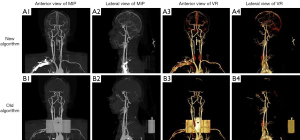

Quantitative comparisons of bone removal scores between 100 and 120 kVp under both algorithms are summarized in Figure 1 and Table 2. With the conventional algorithm, the median score from 3.50 (IQR, 3.50–4.00) to 3.50 (IQR, 3.50–4.00) (P=0.042), and with the deep learning algorithm from 4.50 (IQR, 4.50–4.50) to 4.50 (IQR, 3.50–4.50) (P=0.002). The κ value between reader 1 and reader 2 was 0.760, indicating substantial inter-reader agreement in the subjective scoring. Representative visual comparisons between the new and old algorithms at 100 and 120 kVp are shown in Figures 2,3, respectively. These examples illustrate typical differences in image quality, particularly in the petrous and orbital regions. While these visual cases support the quantitative results, the objective evaluations are detailed in the subsequent figures. These findings suggest that higher tube voltage enhances bone subtraction, thereby improving vascular visualization quality in head and neck CTA.

Vessel branch completeness scores showed no significant differences between 100 and 120 kVp groups (old algorithm: P=0.311; new algorithm: P=0.051; Mann-Whitney U test), as depicted in Figures 2,3. The near-significant result with the latest algorithm suggests a potential trend toward improved peripheral vessel visualization at 120 kVp, warranting further investigation.